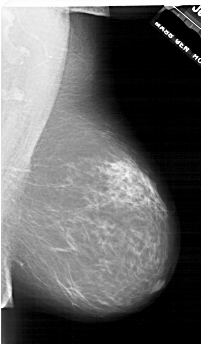

ics_version 1.0 filename A-1743-1 DATE_OF_STUDY 11 7 1996 PATIENT_AGE 69 FILM FILM_TYPE REGULAR DENSITY 3 DATE_DIGITIZED 3 3 1999 DIGITIZER HOWTEK 43.5 SEQUENCE LEFT_CC LINES 6601 PIXELS_PER_LINE 4201 BITS_PER_PIXEL 12 RESOLUTION 43.5 OVERLAY LEFT_MLO LINES 6871 PIXELS_PER_LINE 4516 BITS_PER_PIXEL 12 RESOLUTION 43.5 OVERLAY RIGHT_CC LINES 6871 PIXELS_PER_LINE 3946 BITS_PER_PIXEL 12 RESOLUTION 43.5 NON_OVERLAY RIGHT_MLO LINES 6526 PIXELS_PER_LINE 3811 BITS_PER_PIXEL 12 RESOLUTION 43.5 NON_OVERLAY |